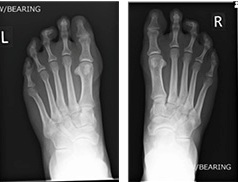

Weight-bearing X-ray (Left) and (Right)

The symptoms were attributed to overload metatarsalgia due to congenitally short first metatarsal bones in both feet. MRI and X-ray investigations can be seen at the right. The report verified there was no bone or joint signal typical of bone stress (or synovitis). Signal consistent with inter-metatarsal bursitis between the 2nd to 3rd inter-metatarsal space (indicated by yellow arrows). X-rays show very slight clawed second toes.